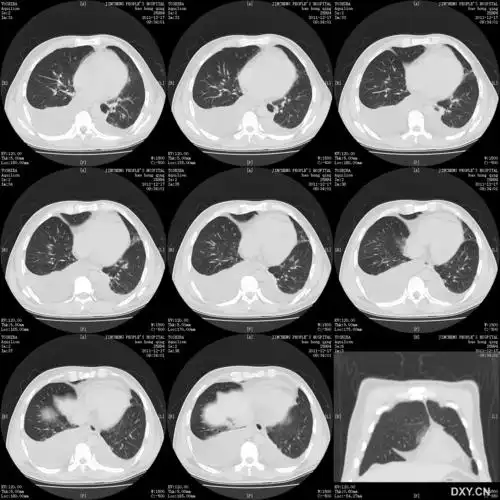

左肺门占位一例

入院复查ct提示:左肺门占位,边缘好像不太光滑,有毛刺征.